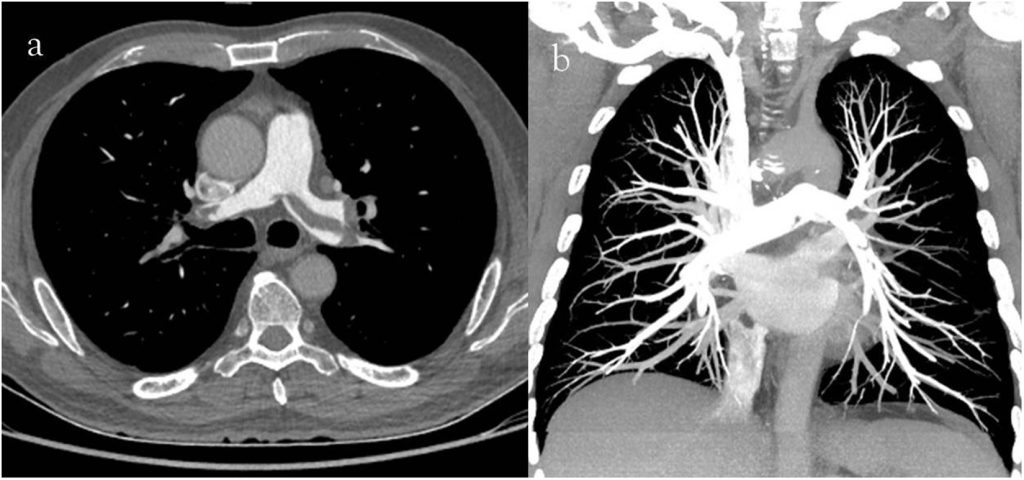

سی تی آنژیو ریه (CT Pulmonary Angiography) یکی از روش های پیشرفته تصویربرداری پزشکی است که برای بررسی دقیق رگ های خونی ریه استفاده میشود. این روش با ترکیب فناوری سی تی اسکن و تزریق ماده حاجب داخل رگ ها، تصاویر سهبعدی و واضحی از عروق ریوی فراهم میکند. هدف اصلی سی تی آنژیو ریه تشخیص مشکلاتی مانند آمبولی ریه (لخته خون در رگ های ریه)، تنگی یا انسداد عروق ریوی است که میتواند عوارض جدی ایجاد کند.

روند انجام این روش در بهترین مراکز سی تی آنژیو ریه معمولاً بدون درد و غیر تهاجمی است. بیمار روی تخت مخصوص دراز میکشد و ماده حاجب از طریق تزریق وریدی وارد جریان خون میشود. سپس دستگاه سی تی اسکن شروع به گرفتن تصاویر میکند. این تصاویر توسط نرم افزارهای پیشرفته پردازش شده و عروق ریوی به صورت دقیق و با جزئیات کامل نمایش داده میشوند.

تفسیر تصاویر سی تی آنژیو ریه یکی از مهمترین مراحل در فرآیند تشخیص بیماری های عروقی و ریوی است که نیازمند دقت و تخصص بالایی است. پس از انجام تصویربرداری، پزشک رادیولوژیست بهترین مراکز سی تی آنژیو ریه با بررسی دقیق تصاویر به دنبال نشانه هایی از انسداد، تنگی یا لخته خون در عروق ریه می گردد.

در تفسیر سی تی آنژیو، پزشک باید کیفیت تصاویر، میزان پرشدگی رگ ها با ماده حاجب، و هرگونه تغییرات غیرطبیعی را بررسی کند. برای مثال، وجود مناطق بدون پرشدگی (که به شکل لکه های تاریک یا خلا در رگ ها دیده می شود) معمولاً نشان دهنده لخته خون است. همچنین، توجه به علائم جانبی مانند التهاب یا تجمع مایع در اطراف ریه نیز اهمیت دارد، زیرا این موارد می توانند در تشخیص علت اصلی علائم بیمار کمک کننده باشند.